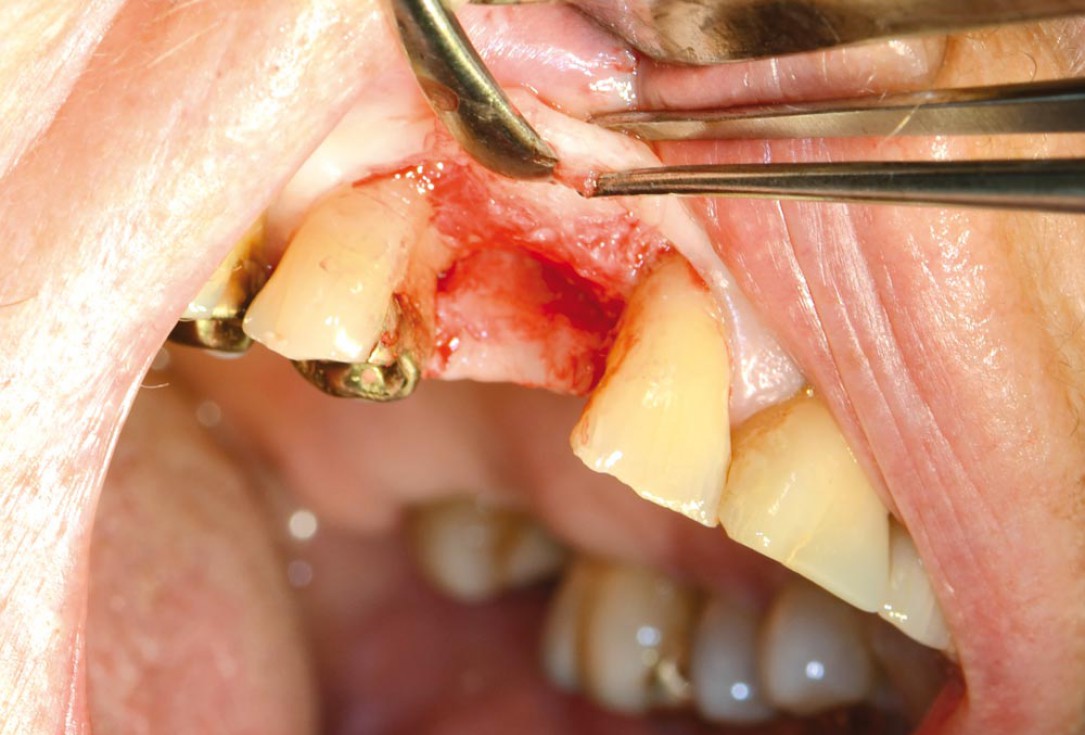

05/12 - Intraoperative situation

Block augmentation with maxgraft® in the maxilla - PD Dr. Dr. F. Kloss